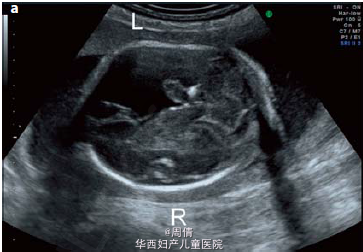

1,2.超声提示在大动脉分叉点以上的降主动脉上有一个动脉瘤,最大直径2cm 3,可见扩大的左脑室和变薄的左侧大脑实质 4,30周时胎儿MRI提示颅腔内的左侧脑室有一个增大的囊性结构